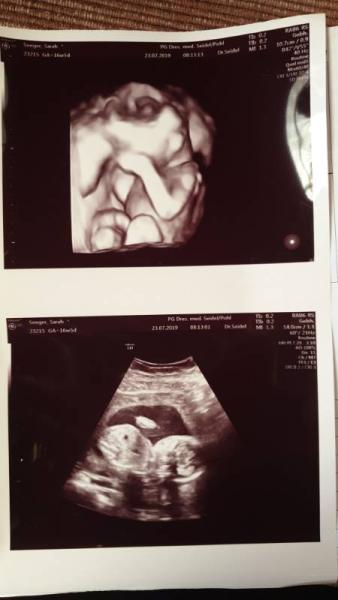

Huhu, Heute hatten wir wieder Termin bei meiner Ärztin, soweit so gut. Diesmal war auch mein Partner dabei und meine Ärztin hatte alles toll gezeigt und erklärt. Als sie dann aber meinte, na vielleicht sehen wir ja heute was es für ein Geschlecht hat, meinte das Baby ganz einfach nöööö. Toll hat natürlich schön die Beine angezogen und die Nabelschnur lag dazwischen. Da wollte meine Ärztin irgendwie daneben schallen, zack hat es noch ein Arm dazwischen geklemmt. Das heißt jetzt für uns 4 Wochen warten (da bin ich dann 21 Ssw) . Ich wollte doch eigentlich shoppen . Hoffentlich bekommen wir dann auch mal unser Outing. Ansonsten war wieder alles top, Baby kann jetzt Fruchtwasser schlucken und war auch wach, hat sich aber dann wieder gedreht. Ich habe heute das erste mal Sodbrennen außerdem spüre ich langsam unseren Krümmel

Bild zu So klein und so Fotoscheu - Forum für Januar - Mamis

So ein schönes 3D Bild Ich kenne das Geschlecht auch noch nicht, ich gebe meinem Nestbautrieb mit gelben und grünen Sachen nach und besorge so Dinge wie Wärmelampe, Badewanne und so... Ok und ich habe Stoffwindeln mit bunten Traktoren drauf....Aber auch Mädchen können Traktoren toll finden

die kleinen Mäuse!!!! Will es sich noch etwas verbergen. Das Bild ist aber toll! Und wenn man sucht, findet man auch schöne Kleidung in Grün oder Rot. Sowas passt immer gut zu Jacken oder Outdoorkleidung. Also zum Schoppen findest du bestimmt ganz viel